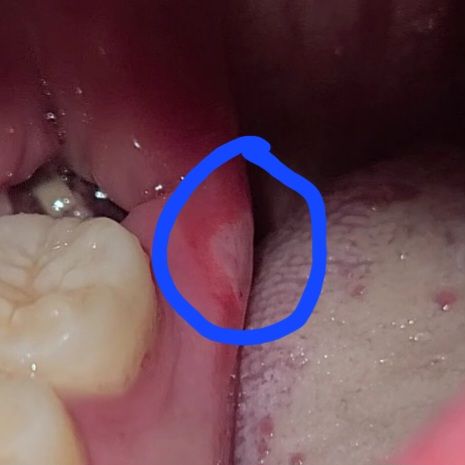

사랑니 발치 후 측면 잇몸이 따갑습니다

사랑니 발치 후 6일정도 되었습니다

근데 잇몸 옆에 허연 부분이 보이더니 밥 먹을때 혀가 닿게 되면 상당히 따갑고 아픕니다

이게 뭔지 알 수 있을까요?

발치를 할때 마취를 하면 압력때문에 저렇게 생길수도 잇고 혀를 미는 과정중에 구내염이 생겻을 가능성도 있습니다.

발치를 하고 나면 자주 나타나는 일종의 구내염입니다. 해당 부위의 자극이 심해서 입 안에 나타난 입병의 일종이며 구내염입니다. 대부분이 시간이 지나면 저절로 회복됩니다. 따라서 크게 걱정하지 않으셔도 됩니다.

해당부위에 구내염이 생긴 것으로 보이며, 이 경우 헥사메딘이라는 소독약으로 입안을 헹구어 주는 것도 도움이 될 수 있습니다. 만약 통증 및 붓기가 지속시에는 치과 진료를 받길 권합니다.